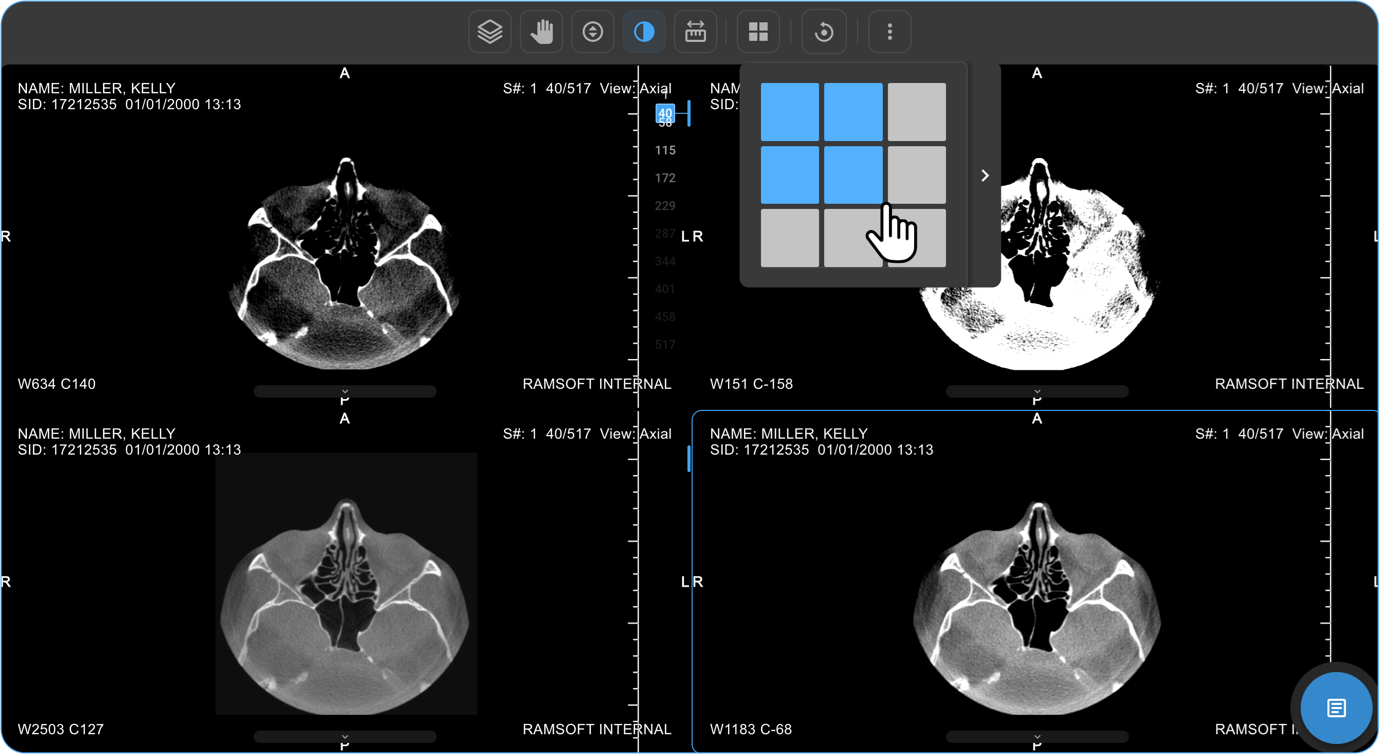

How Do I View Multiple Images or Series in Different Layouts?

• If there are multiple images or a series of images, you can customise the display layout to enhance your viewing experience.

• Locate and click on the Change Layout icon in the image viewer toolbar at the top of the screen.

vai

• Select the desired layout format to switch between a single-frame view and a multi-frame display for comparing multiple images simultaneously.